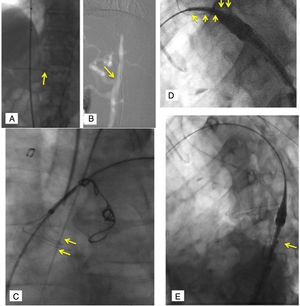

Postoperatorio y seguimientoEn el postoperatorio, 3 pacientes presentaron síndrome postimplante, uno cefalea posdrenaje espinal y otro, miopatía generalizada (estancia prolongada). En todos los pacientes se realizó TAC de control previo al alta, se consideró éxito si no había endofugas tipos I/III ni migración / complicación endoprótesis; la existencia de endofuga retrógrada en las disecciones no fue considerado fracaso. En solo un paciente se apreció endofuga tipo Ia (caso 5); en la TAC de control un mes más tarde había desaparecido con inicio de remodelado del saco aneurismático (fig. 6).

Endofuga inicial tipo Ia (caso 5): A) Angiografía en proyección de trabajo ASI tras implante Castor™, sin endofuga aparente. Prótesis ligeramente rotada, ya que se visualiza el 8 de la curvatura menor no perfectamente alineado. B) Tomografía axial computarizada postoperatorio inmediato: endofuga Ia con relleno del saco aneurismático. C) Tomografía axial computarizada en seguimiento (un mes): ausencia endofuga Ia. D) Tomografía axial computarizada en seguimiento (un mes): reconstrucción 3D (volumen rendering).